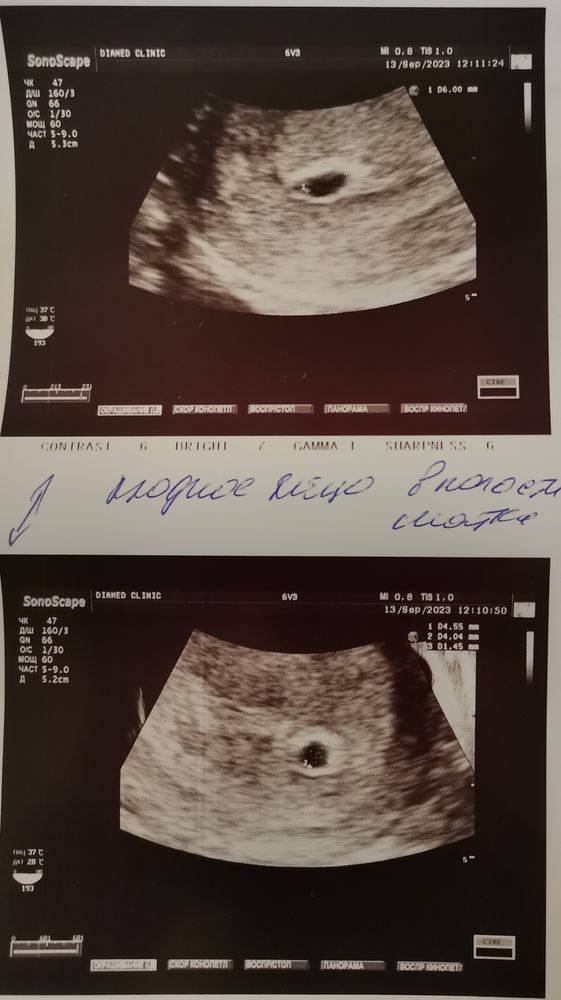

Сегодня у меня 7.1 неделя по менструации, пошла становиться на учёт и заодно сделать узи! В последний раз я видела малыша 12 дней назад, тогда его ещё там